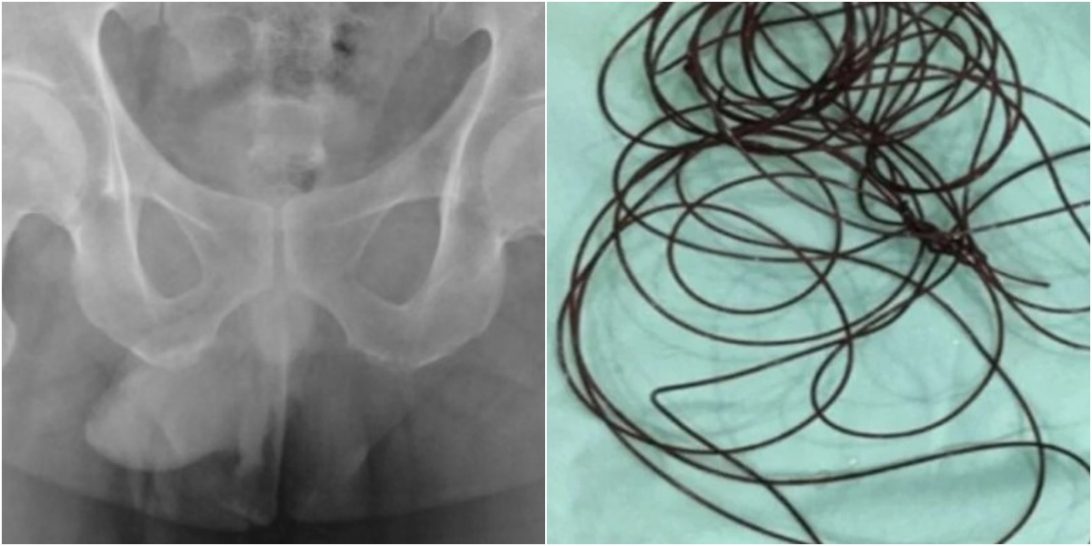

INDONÉSIA | Um homem, de 37 anos, deu entrada em um hospital na província de Java Oriental, Indonésia, após introduzir um cabo de nylon de dois metros de comprimento no pênis. Para a retirada do fio, a equipe médica precisou realizar uma pequena cirurgia de cistoscopia (procedimento endoscópico feito nas vias urinárias). As informações são do UOL.

Após a realização de alguns exames, foi identificado que havia um fio de nylon (utilizado na produção de bijuterias) na região da uretra – tubo que leva a urina da bexiga para o exterior.

Então, os médicos da unidade de saúde decidiram inserir um cateter para incentivar a irrigação ativa do pênis e assim retirarem o fio introduzido. No entanto, essa manobra não surtiu efeito e foi necessário realizar uma pequena cirurgia.